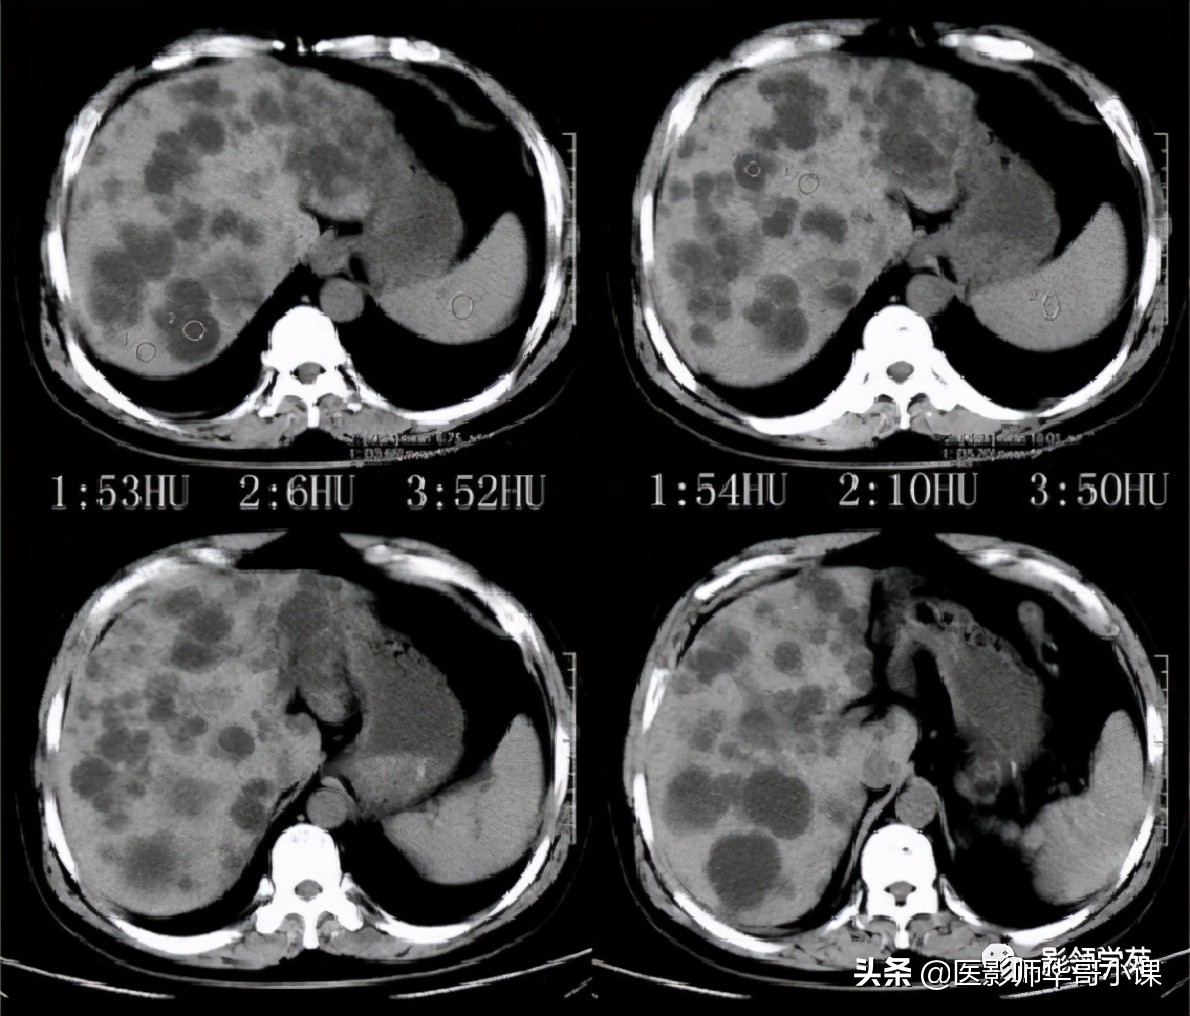

Caroli病影像诊断要点

1、肝内胆管不成比例的扩张,并与正常胆管相间,这是鉴别本病与继发性阻塞性肝内胆管扩张的关键所在,后者表现为从中央向末梢逐渐变细的、成比例的扩张。

2、“中心点征”是又一重要的征象,是指囊肿阴影内的小点状软组织影像,平扫密度等于或高肝实质,在T2WI序列上呈环状低黑信号,中央区呈圆柱稍高信号,其病理基础是门静脉分支被胆管扩张的囊壁包绕,并在切面上呈轴位投影。Seth等认为“中心点”征象的出现足准确的诊断本病。